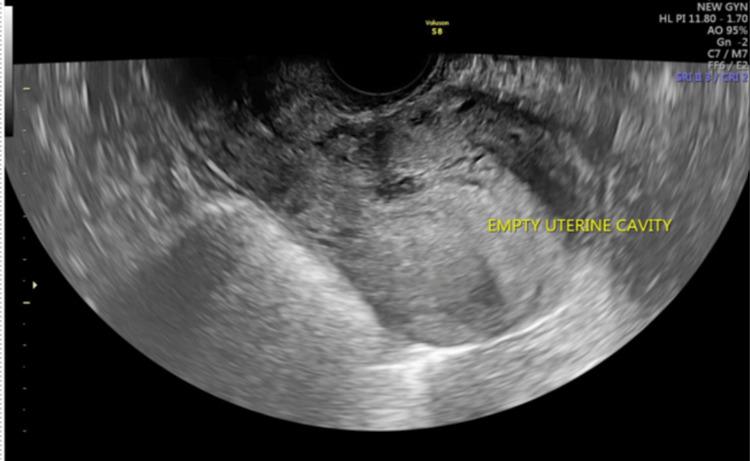

Ectopic pregnancy in the scar of a previous cesarean section contributes to significant maternal morbidity in the first trimester due to a significantly higher risk of uterine rupture if left undetected. The routine scans done in the first trimester serve as an important screening tool in the detection of such an ectopic pregnancy. Early detection can aid in making a paradigm shift from a surgical to a more conservative approach for the management of such pregnancies. Here, we report a case of a cesarean scar pregnancy diagnosed in the sixth week of gestation which was managed non-surgically with methotrexate and intracardiac potassium chloride injection.

既往剖宫产瘢痕处的异位妊娠,若未被发现,由于子宫破裂风险显著更高,会在孕早期导致严重的孕产妇发病。孕早期进行的常规扫描是检测此类异位妊娠的重要筛查工具。早期发现有助于将此类妊娠的管理模式从手术治疗转变为更保守的方法。在此,我们报告一例在妊娠六周时诊断出的剖宫产瘢痕妊娠,该病例通过甲氨蝶呤和心内注射氯化钾进行了非手术治疗。